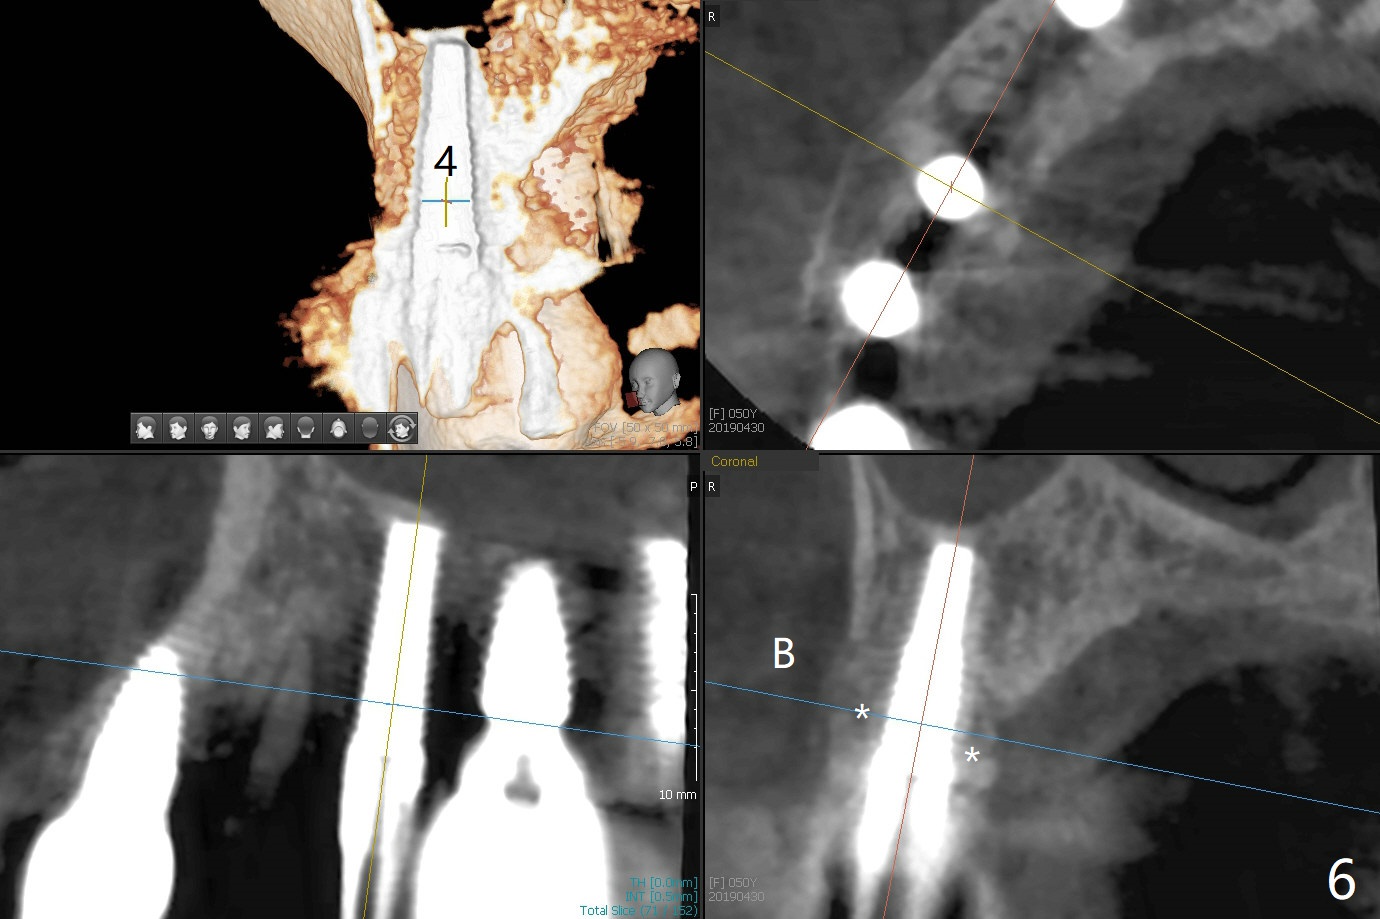

After osteotomy using bone-level implant guide at #4, the crown and abutment at #3 has to be removed to place a 4x14 mm tissue-level dummy implant because of the narrow space of #4 and implant placement angulation (Fig.1). Following initial placement of a final 4x17 mm implant and bone graft (Fig.2 *), the crown and abutment of #3 and the guide are reseated for correct implant trajectory. The guide has to be removed for final depth control. With the same mode, a 5x17 mm tissue-level tap is used at #2 following bone-level osteotomy with guide. A 5x14 mm tissue-level implant is placed with >50 Ncm (later placed deeper), while more bone graft is inserted mesial of #4 implant with a 3.5x5 mm abutment (Fig.3 *). Bone graft is introduced into the sinus using guided sinus lift kit (Fig.4,5 (CT sagittal and coronal sections)) * (D: distal, P: palatal)). The coronal half of the implant at #4 is covered by bone graft (Fig.6 *) buccal (B) and palatal within the deep socket. The implants at #2 and 4 seem to have osteointegrated nearly 5.5 months postop (Fig.7,8 (BW)). A 4.5x5 mm unipost is later placed at #2 with long chamfer margin. It appears that the abutment at #3 is wide. The hex is worn. It changes to a 5.5x7(4) mm one. After abutment adjustment for parallelism, a provisional FPD is fabricated. The latter will be adjusted for papilla formation between implants to reduce food impaction.